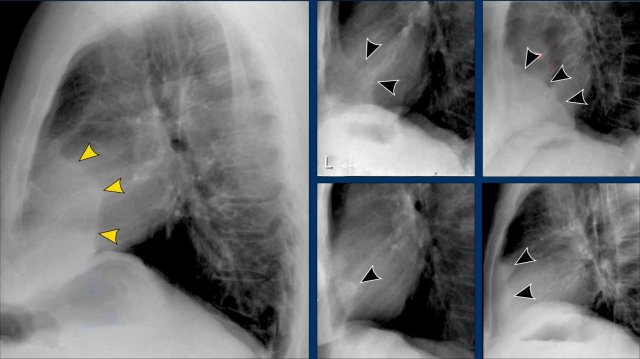

Displacement of the Azygoesophageal Line (1) – Hiatal hernia

A hiatal hernia (arrowheads) is the most common cause of displacement of the azygoesophageal line as seen on the PA-view.

Notice the air within the hernia on the lateral view (black arrow).